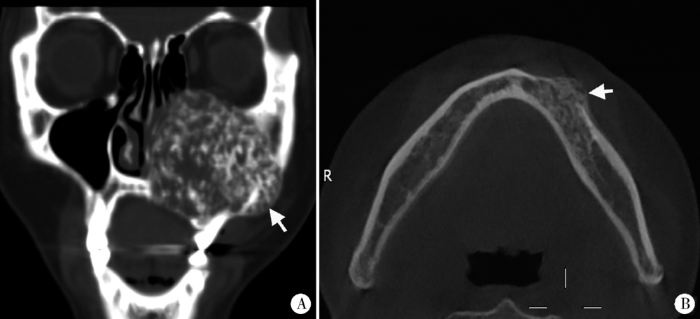

图6

典型实性多囊型(A)和单囊型(B)成釉细胞瘤

Figure 6

Classic solid/multicystic (A) and unicystic (B) ameloblastomas

The solid/multicystic type is composed of multilocullar cyst (white arrow, A) and solid content (black arrow, A). The unicystic type shows homogenous cyst (white arrow, B).